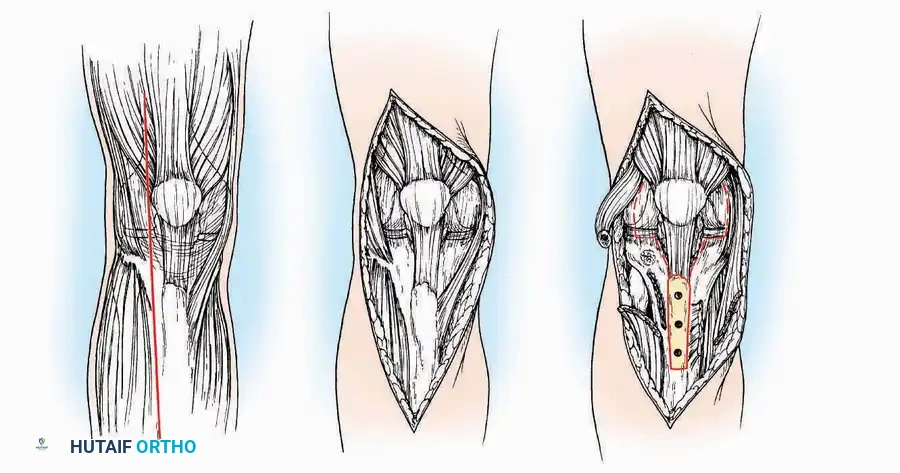

Lateral Approach (Extensile Lateral)

This is the workhorse approach for open reduction and internal fixation (ORIF) of displaced intra-articular calcaneal fractures.

Indications: ORIF of calcaneus fractures, lateral wall exostectomy, subtalar arthrodesis.

Positioning: Lateral decubitus with the operative leg up, or supine with a large bump under the ipsilateral hip to internally rotate the leg.

Surgical Technique:

* Incision: Begin the incision on the lateral margin of the Achilles tendon near its insertion. Extend it distally to a point 4 cm inferior and 2.5 cm anterior to the lateral malleolus. (For trauma, a classic L-shaped extensile incision is often used, dropping straight down anterior to the Achilles, then curving gently toward the base of the 5th metatarsal).

* Superficial Dissection: Divide the superficial and deep fasciae. It is imperative to create a "full-thickness" flap containing skin, subcutaneous fat, and periosteum to prevent flap necrosis.

* Nerve Protection: The sural nerve crosses the proximal and distal limbs of this approach. It must be identified and protected within the anterior flap.

* Deep Dissection: Isolate the peroneal tendons (longus and brevis). Incise and elevate the periosteum below the tendons to expose the lateral wall of the calcaneus.

* Tendon Management: If severe deformity or infection is present, the peroneal tendons may be divided via Z-plasty and repaired at the conclusion of the case, though this is rarely necessary in modern fracture care.